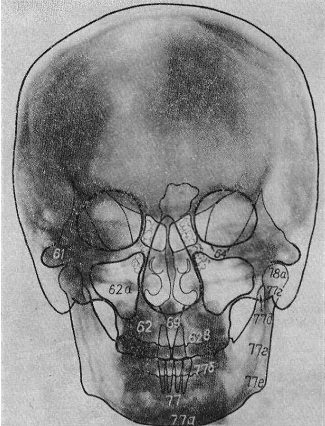

Рентгенография небного шва: Медицинские исследования и диагностика